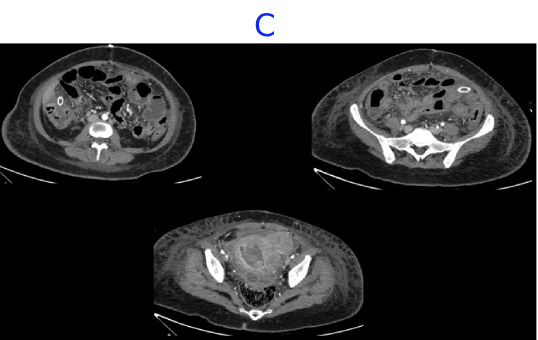

• C. CECT ABDOMEN AND PELVIS- DAY 7- STATUS POST EXPLORATORY LAPAROTOMY AND PERITONEAL LAVAGE

• D. Bulky uterus with a hypodense submucosal lesion protruding into the endometrial cavity from the fundus showing heterogeneous enhancement - infected vs infarcted fibroid. Abnormally enhancing endometrial lining with hypodense content within the endometrial cavity - possible endometritis with pyometra. Pelvic peritonitis with residual trace fluid in the pelvis. Interval resolution of pneumoperitoneum. Abdominal drains in situ.